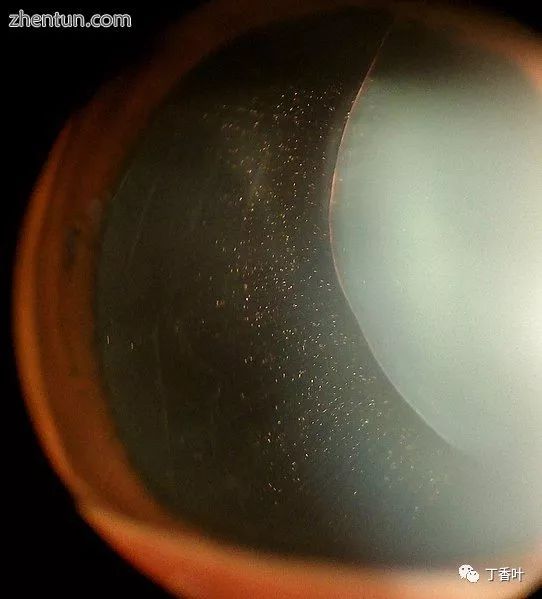

马凡氏综合症中的异位症:可见Zonular纤维。

Marfan综合征中的晶状体脱位,晶状体呈肾形,并靠在睫状体上

在Marfan综合征中,眼睛的健康可以在很多方面受到影响,但主要的变化是部分晶状体脱位,其中晶状体移出其正常位置。[11]这是因为睫状小带的弱点,即将镜片悬浮在眼内的结缔组织束。导致马凡综合征的突变削弱了小带并导致它们伸展。下部小带最常被拉伸,导致镜片向上和向外移动,但它也可以在其他方向上移动。近视和视力模糊是常见的,但是如果镜片高度半脱位,也可能导致远视。通过使用裂隙灯生物显微镜,可以在80%的Marfan综合征患者中临床检测晶状体的半脱位(部分脱位)。如果晶状体半脱位是微妙的,则可以使用高分辨率超声生物显微镜成像。